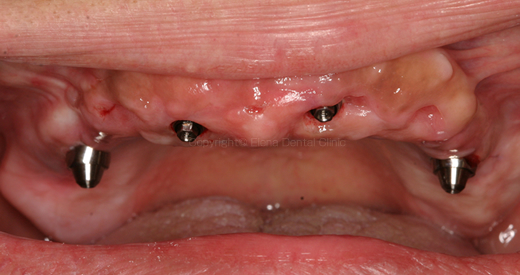

4本のインプラントを埋入した状態です。

術後のレントゲン画像です。前歯部に2本、臼歯部に2本傾斜埋入できました。